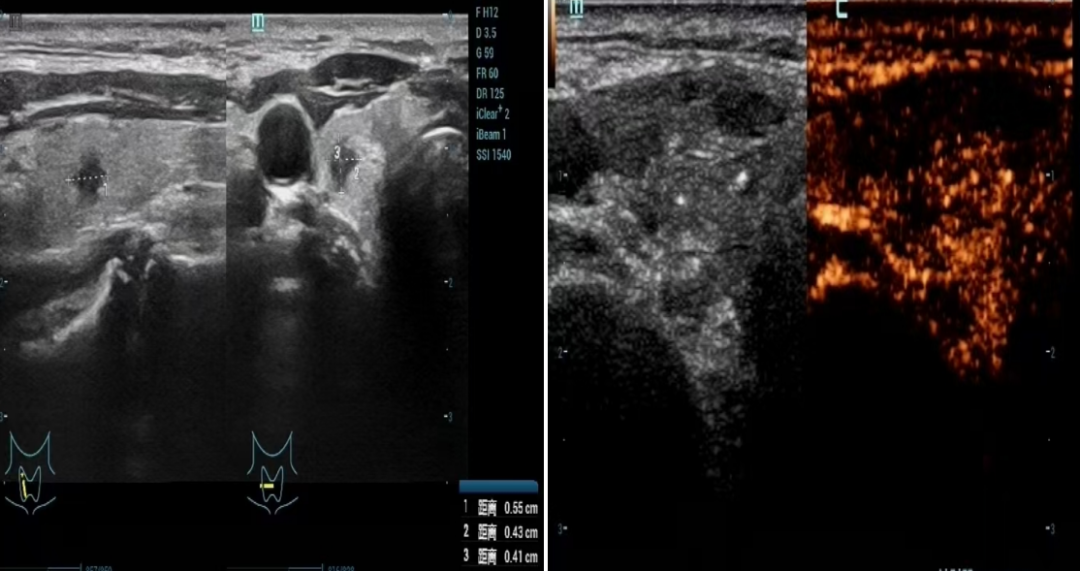

张先生的术前结节大小约为0。5*0。4*0。4cm,超声造影显示结节呈快进快出、不均匀性低增强表现。手术步骤包括:消毒、铺巾、局部麻醉、注射0。9%生理盐水建立隔离带、穿刺活检。治疗过程中,消融针正中贯穿结节,随后启用适当功率消融针移动连续扩大消融范围,最后封闭针道、拔针。术后即刻超声造影评估显示消融区域完全无增强,局部冰敷后术毕。